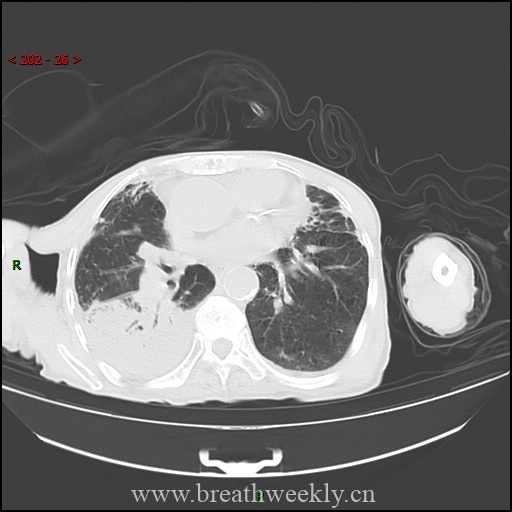

头颅CT除外颅内肿块及脑出血。脑及颈椎MRI(增强)除外CT隐性病灶,但发现右侧胸廓入口处囊性病灶。颈部超声及增强胸部CT:右侧上纵隔囊性占位,位于甲状腺右叶后下方,内见结节性实性成分及上极供血血管。胸部CT示前纵隔预期胸腺位置无异常软组织,提示胸腺脂肪萎缩。

临床过程:因纵隔病灶位置位于甲状腺右叶后下方,术前考虑异位胸腺瘤或异位甲状旁腺腺瘤。CT及超声示无claw sign,排除甲状腺来源。99mTc-Sestamibi显像定位病灶。MG予糖皮质激素及IV免疫球蛋白治疗效果良好;高钙血症予IV补液及cinacalcet治疗。最终行机器人辅助纵隔甲状旁腺腺瘤及胸腺切除术,病理确诊甲状旁腺腺瘤。术后患者恢复良好。